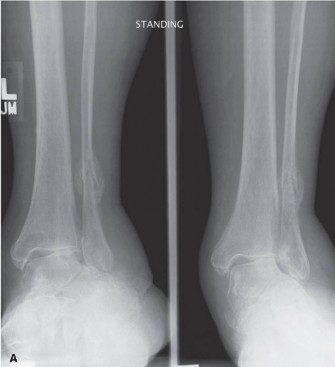

The ankle joint, a hinge joint, is formed by the distal tibia, fibula, and talus. Key radiographic assessments include:

* Ankle mortise integrity: Measured by the tibiofibular clear space, medial clear space, and talocrural angle on AP views, indicating syndesmotic stability.

* Ankle fractures: Bimalleolar, trimalleolar, or syndesmotic injuries (e.g., widened medial clear space, tibiofibular clear space > 6mm on AP/mortise views).

| Ankle Fractures | Displaced (>2mm) articular incongruity, bimalleolar/trimalleolar, syndesmotic disruption (medial clear space >4mm, tibiofibular clear space >6mm, talar shift) | Non-displaced unimalleolar (stable), avulsion fractures not involving weight-bearing surface, stable stress fractures. |

Thorough pre-operative planning is the cornerstone of successful foot and ankle surgery, directly informed by comprehensive radiographic evaluation. Beyond standard anteroposterior (AP), lateral, and oblique views, specific stress views or weight-bearing radiographs are often critical. For complex deformities or intra-articular fractures, advanced imaging such as computed tomography (CT) with 3D reconstructions and magnetic resonance imaging (MRI) may be indispensable to delineate fracture patterns, assess articular congruity, quantify deformity, and evaluate soft tissue injury (e.g., ligamentous tears, cartilage damage).